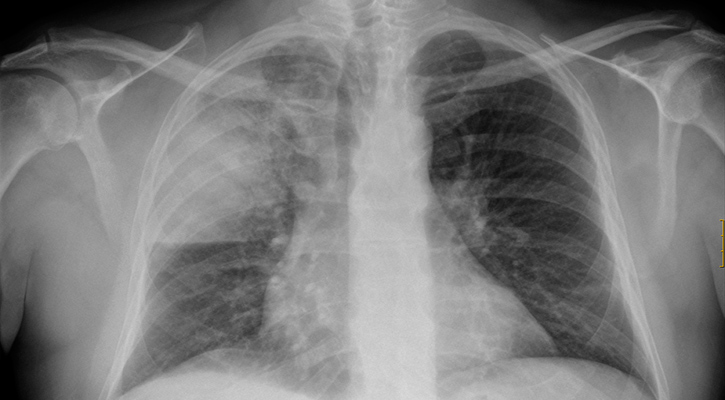

En lo que va del año la incidencia de enfermedades respiratorias se ha incrementado en casi un 2% con relación al mismo período en 2024, aunque los casos que han evolucionado a una condición más grave, han crecido hasta en un 42%, reconoció la secretaria de Salud de Baja California Sur, Ana Luisa Guluarte Castro.

Sin embargo, expuso que aunque el crecimiento en ese renglón podría considerarse mínimo, destaca que los casos que se complicaron por neumonías y bronconeumonías, ascendieron de 117 en la sexta semana del 2024 a 167 en este mismo período en 2025.